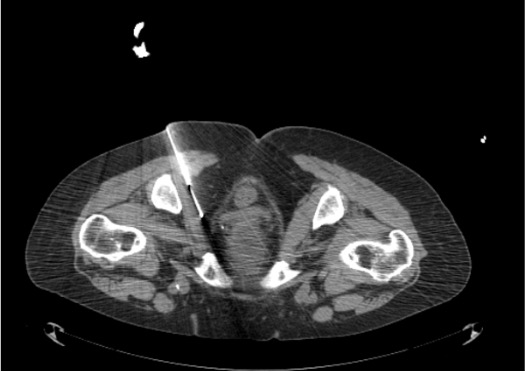

- Primary target (Alcock’s canal approach): medial border of obturator internus muscle in the pudendal canal — nerve runs as posterior-most structure of the neurovascular bundle; intermediate density compared to adjacent vessels

- Alternative target (ischial spine approach): nerve located between sacrospinous and sacrotuberous ligaments where they converge at ischial spine; injectate distributes anteromedially into Alcock’s canal

- Pudendal artery and vein run adjacent — aspirate before injection; always confirm no vascular opacification with dilute contrast

- Rectum lies medial — CT confirms needle tip position prior to injection